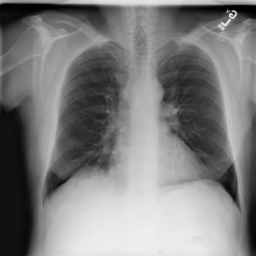

Anomaly detection is the problem of recognizing abnormal inputs based on the seen examples of normal data. Despite recent advances of deep learning in recognizing image anomalies, these methods still prove incapable of handling complex medical images, such as barely visible abnormalities in chest X-rays and metastases in lymph nodes. To address this problem, we introduce a new powerful method of image anomaly detection. It relies on the classical autoencoder approach with a re-designed training pipeline to handle high-resolution, complex images and a robust way of computing an image abnormality score. We revisit the very problem statement of fully unsupervised anomaly detection, where no abnormal examples at all are provided during the model setup. We propose to relax this unrealistic assumption by using a very small number of anomalies of confined variability merely to initiate the search of hyperparameters of the model. We evaluate our solution on natural image datasets with a known benchmark, as well as on two medical datasets containing radiology and digital pathology images. The proposed approach suggests a new strong baseline for image anomaly detection and outperforms state-of-the-art approaches in complex medical image analysis tasks.